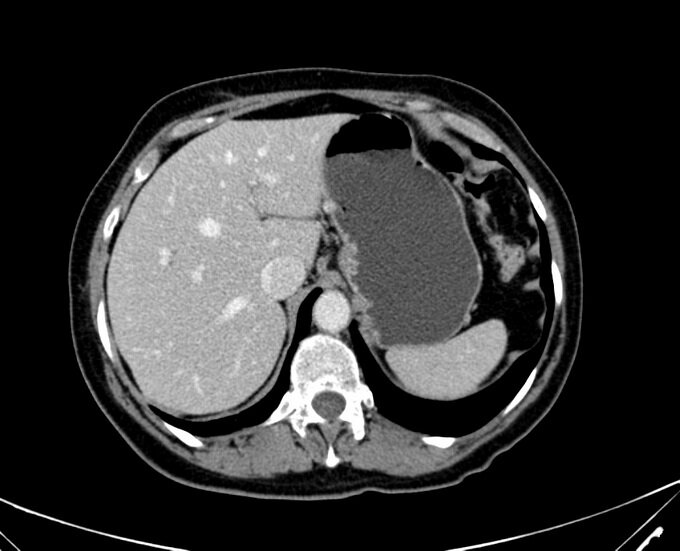

МРТ печени в рамках комплексного обследования органов брюшной полости помогает врачам своевременно выявить многие заболевания и патологии, проконтролировать ход назначенного лечения, определить четкие границы травмированных участков или опухолей, увидеть общее состояние органа и окружающих его тканей. Послойное сканирование в рамках МР-холангиографии дает специалистам информацию о работе печени и желчевыводящих протоков. Оно служит основанием для выдачи врачебного заключения и рекомендаций по дальнейшим действиям пациента при заболеваниях желчевыводящих путей. Магнитно-резонансная томография печени с контрастом делает изображение печени более ярким и четким, поэтому часто применяется для определения границ опухоли, стадирования рака и выявления мест локализации метастаз. Решение о правильном способе сканирования данного органа обычно принимает лечащий врач, исходя из целей диагностики и первичного диагноза. Если пациент сам принял решение пройти томографию печени в качестве профилактики, начинать свой диагностический путь лучше с базовой МРТ брюшной полости без контраста.

• опухолей добро- и злокачественного генеза, включая печеночные кисты, гранулемы печени, гемангиомы, первичный или метастатический рак печени;